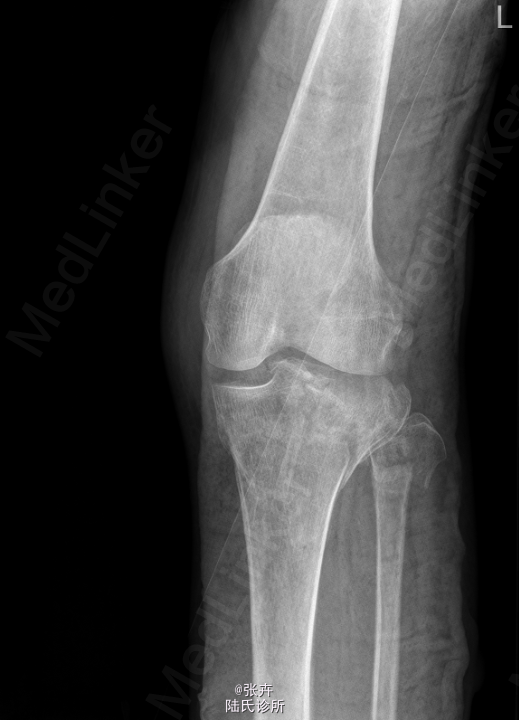

患者,男,50岁,因“外伤致左膝肿痛伴活动受限1天”入院。 患者1天前在工地干活时摔伤,左膝着地,当即感左膝疼痛,呈持续剧痛,左膝关节活动受限,左下肢不能站立及行走,无左下肢麻木。我院CT提示:左侧胫骨平台及左侧腓骨头粉碎性骨折,左膝关节积液、积脂血症。建议手术治疗,遂拟“左胫骨平台骨折”收住入院。

查体:左小腿上段肿胀明显,皮温不高,局部皮肤张力性水泡,无出血、渗出等,左膝关节活动受限,关节间隙,压痛明显。 我院CT提示:左侧胫骨平台及左侧腓骨头粉碎性骨折,左膝关节积液、积脂血症

初步诊断:左胫骨平台骨折。行左胫骨平台骨折切复内固定+人工骨植骨术。